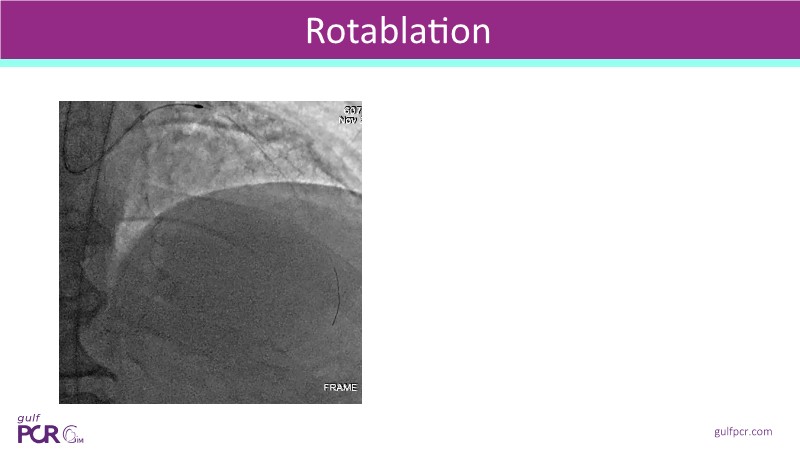

- To optimise lesion preparation: when NIRS reveals high lipid burden or calcific nodules, operators can choose atherectomy, intravascular lithotripsy, or specialised balloons to modify the lesion before stenting